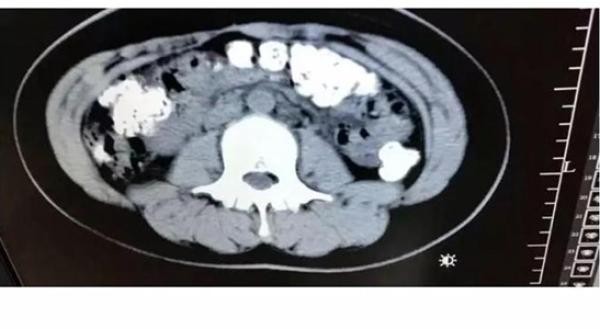

掃瞄結果令人大吃一驚,小沈的胃部、橫結腸、升結腸、降結腸、乙狀結腸,甚至一直到肛門,都發現了顆粒狀陰影,數量更超過100粒。後來醫生詢問小沈最近有沒有進食不易消化的食物。小沈才吞吞吐吐說出5天前曾喝過珍珠奶茶。